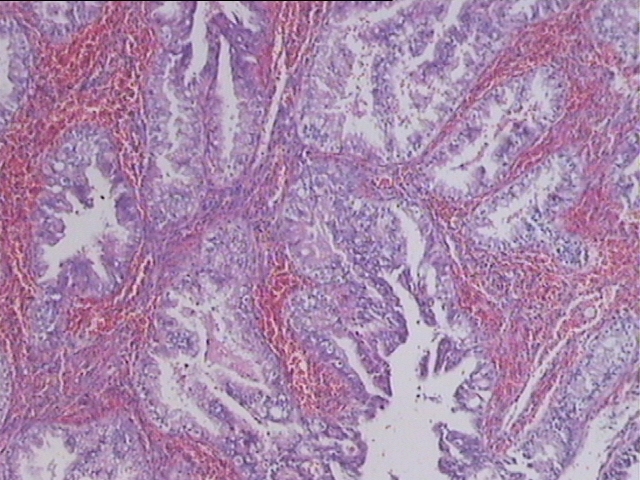

子宫内膜复杂性增生伴非典型性增生,部分癌变?

性别

女

年龄

33岁

临床诊断

异常子宫出血

一般病史

阴道淋漓出血15天

标本名称

子宫内膜

大体所见

破碎膜样组织一堆,3.0*3.0*.5cm。

非典型性增生

分泌晚期形态宫内膜

就这两张图片而言,不敢报癌。